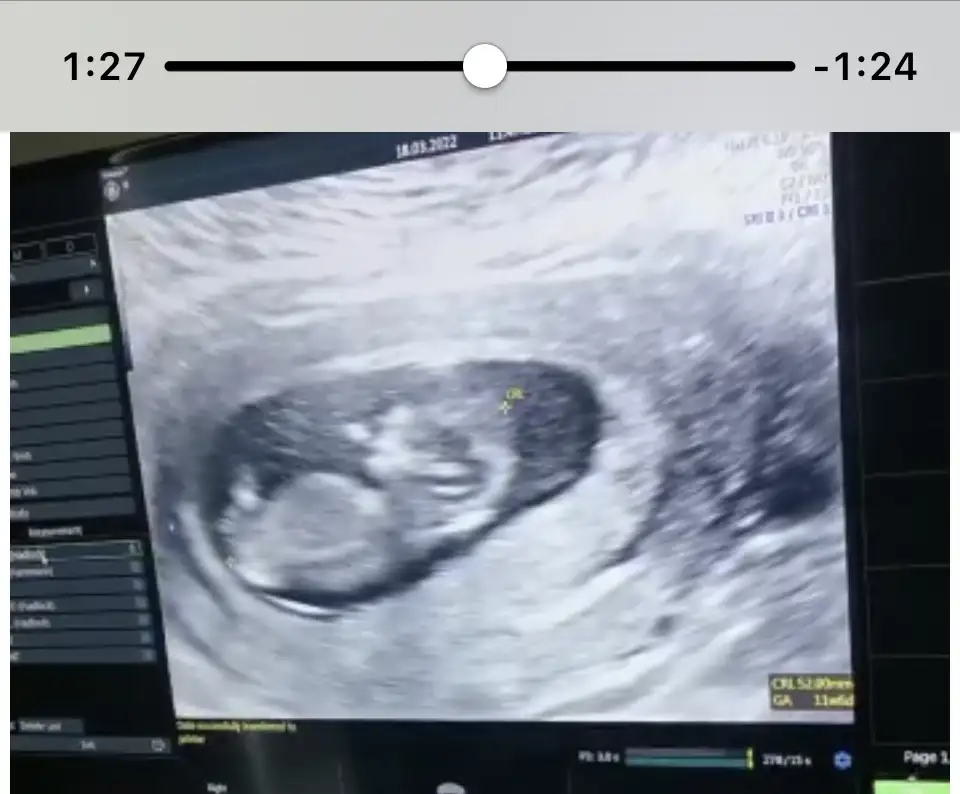

Canım 12+4degil misin sen hamilelik takviminde yazdığına göre. Eğer kızsa zaten biraz daha geçince netleşir 14. Hafta da falan. Bakalım bende yarın gidicem 12+3 oluyor tahminde bulunurum demişti amaBacım cinsiyet sormak için gittiğimi biliyordu. 11+4 üm baktı iyice sana net bişey söyleyemem şuan bi tahmin beklediğin için kız olduğunu söyleyebilirim ama net değil 14-16. haftanda yine görün net öğrenelim dedi.

kuzu bu erkek gibi duruyor öğrenince yaz olur muKarından ultrason 11+4